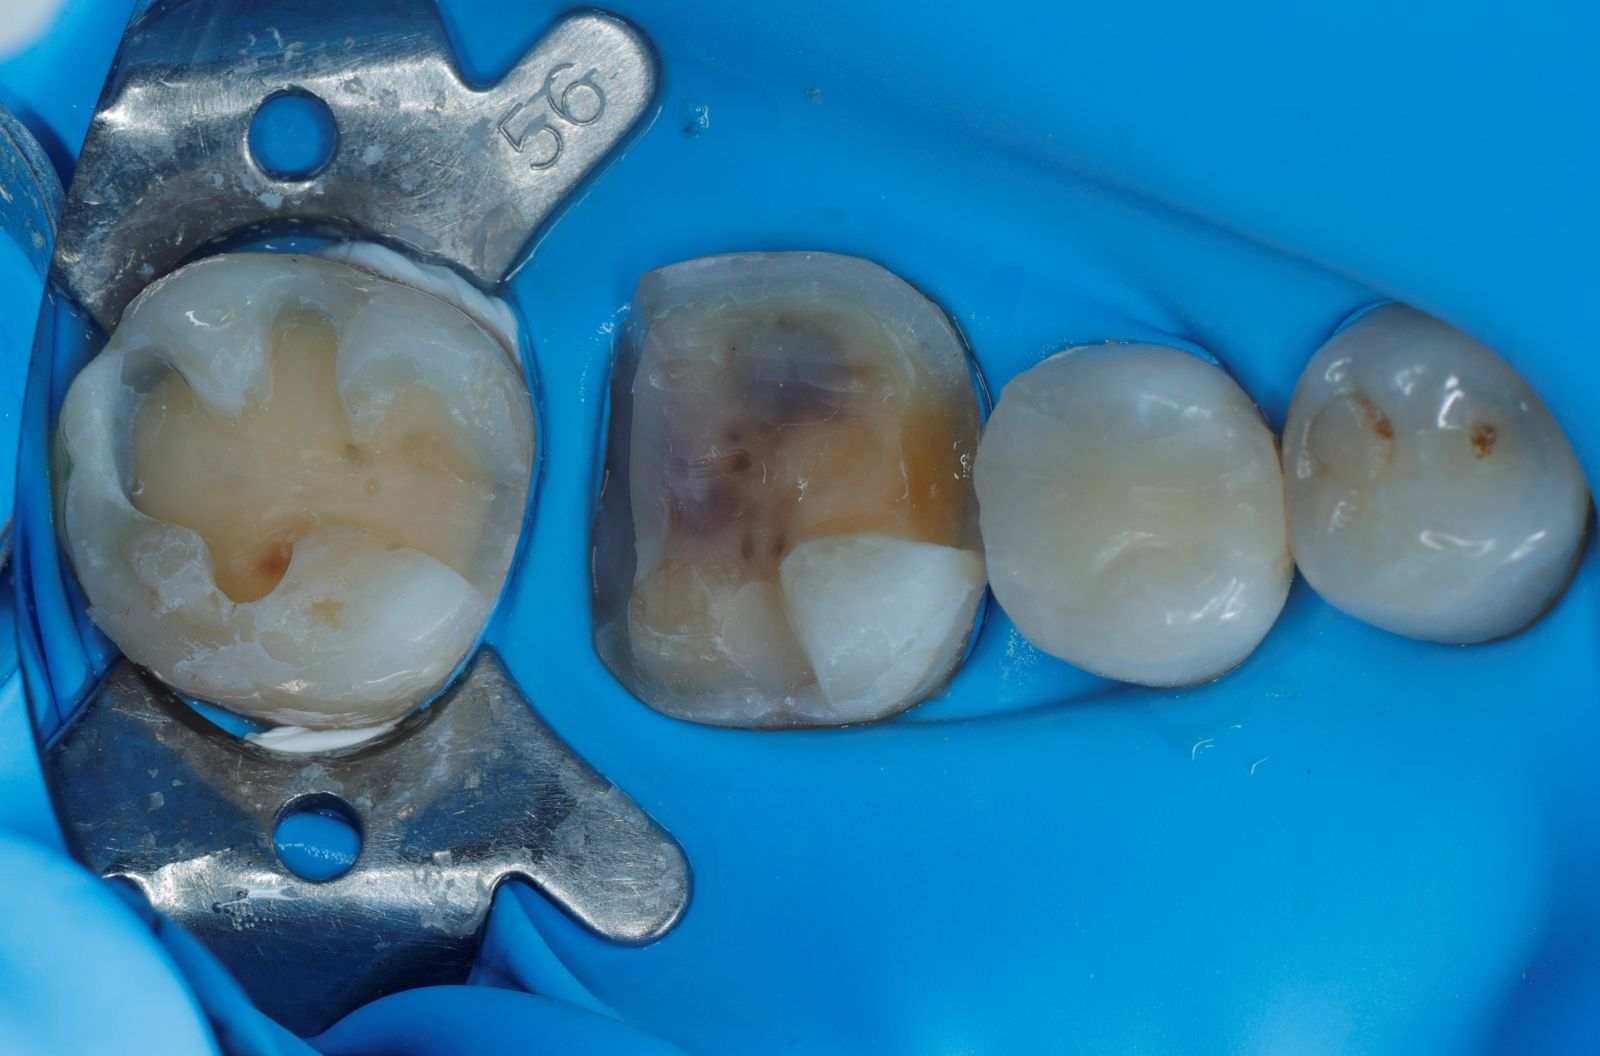

【 案 例 四】